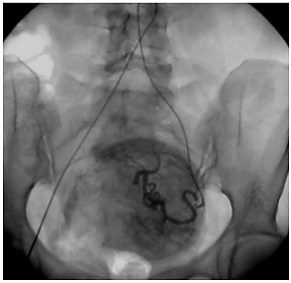

Эмболизация маточных артерий (ЭМА) — способ лечения миомы матки без хирургической операции. Эффект достигается за счет перекрытия кровотока в узлах миомы с помощью специального препарата, который вводится в артерии матки по тонкой трубке (катетеру) через бедро. Препарат содержит мелкие шарики (эмболы), которые перекрывают артерии миомы, после чего она погибает в течение нескольких часов. Эмболизация маточных артерий позволяет во многих случаях отказаться от необходимости удаления матки при миоме и сохранить репродуктивную функцию.

При миоме ЭМА вызывает прекращение кровотока по ветвям маточных артерий, кровоснабжающим миому. Разный диаметр питающих миому ветвей и ветвей, питающих миометрий, приводит к минимальному воздействию на сосуды неизмененного миометрия. После прекращения кровоснабжения мышечные клетки, формирующие миому, гибнут. В течение нескольких недель происходит их замещение соединительной тканью. Затем в процессе «рассасывания» этой ткани происходит значительное уменьшение и/или полное исчезновение узлов, а симптомы миомы проходят.